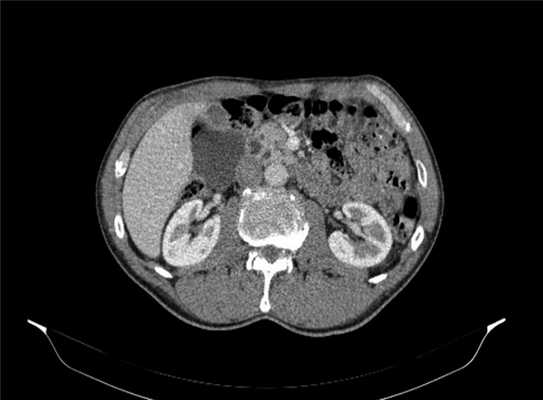

После консультации специалистами клиники в амбулаторном порядке выполнен ряд исследований. При спиральной компьютерной томографии органов брюшной полости обнаружены признаки кистозного образования в области ворот печени (более вероятно киста ОЖП) от 11.05.17 (рис. 2). Ввиду неоднозначности трактовки 30.05.17 выполнена магнитно-резонансная томография в режиме холангиографии, при которой визуализировалась киста брюшной полости размерами 66×44×48 мм с локализацией в области ворот печени, оттесняющая желчный пузырь кнаружи. Образование прилежало к нижней поверхности печени, к передним отделам и сосудистой ножке правой почки, нижней полой вене, к общему печеночному протоку без сужения их просвета, к головке поджелудочной железы и к стенке двенадцатиперстной кишки (ДПК).

Рис. 2. Данные спиральной компьютерной томографии органов брюшной полости с внутривенным контрастированием.

Следует отметить, что после введения гепатотропного парамагнитного контрастного вещества накопление его в сосудистой фазе сканирования не определялось.